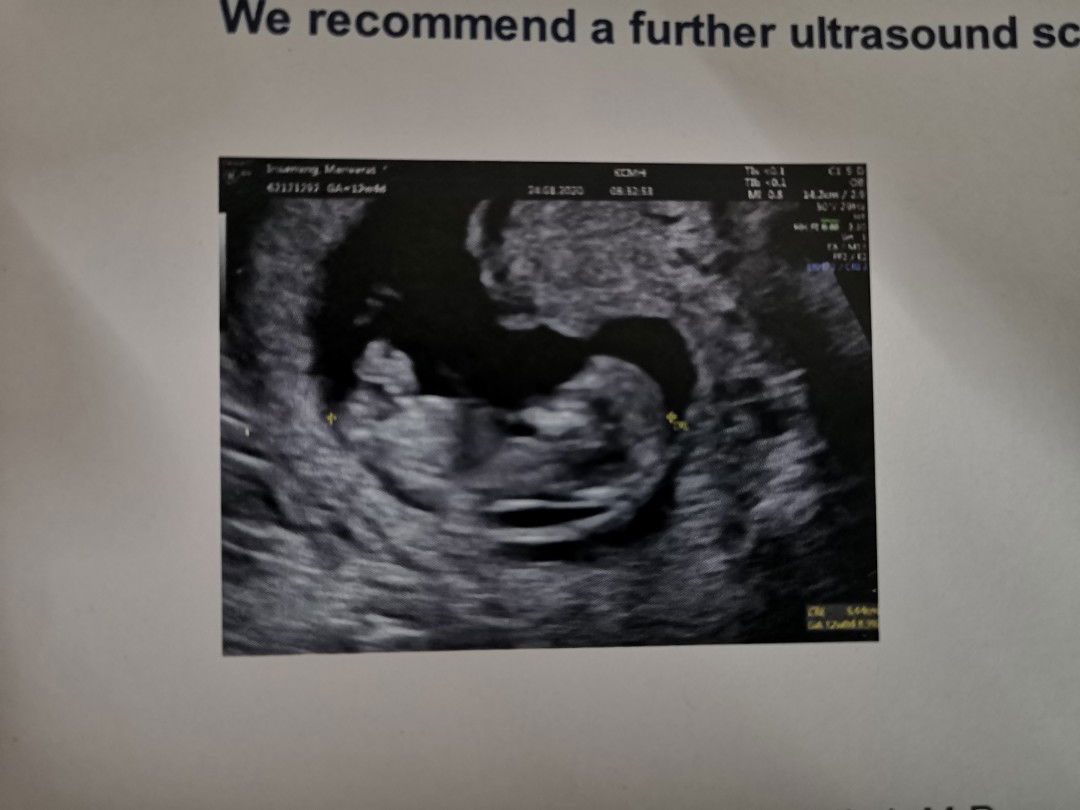

หลังจากผ่านมา1สัปดาห์เมื่อวานได้ไปตรวจดาวน์ซินโดรม ตอนเเรกเเม่ใจหายมากน้องนอนนิ่งไม่ขยับตัวเลยหมอก็ขยับที่ซาวด์ไป-มาสักพักประมาณ2นาที ปรากฎว่าน้องยังอยู่หัวใจเต้น161/นาที น้องดิ้นเเละบิดขี้เกียจ เก่งมาก? พลิกตัวหันหลังให้เเม่กับหมอด้วยสงสัยรำคาน? เเต่อาการเลือดออกกระปริบกระปรอยยังอยู่ วันนี้นัดฉีดยากันเเท้งเข็มที่2 มีอาการปวดท้องหน่วงๆนิดหน่อย #ได้เเต่ภาวนาให้น้องปลอดภัยออกมาลืมตาดูโลกกับเเม่กับพ่อเเละครอบครัว #ทุกครั้งที่ได้ยินเสียงหัวใจเเม่ก็ดีใจมาก